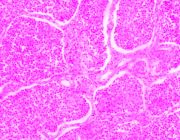

| 2021年12月10日 (五) 13:23 | 24号切片-小叶性肺炎-镜下观3.jpg (文件) |  |

154 KB | Cirno.9 | 基于MsUpload的文件上传 | 1 |